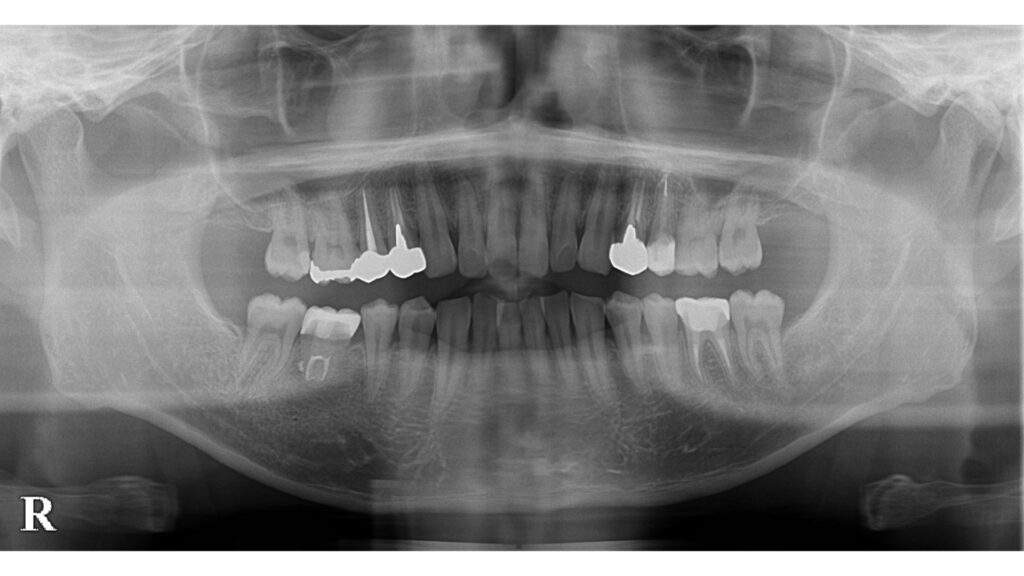

左下奥歯に違和感を訴えて来院されました。

銀歯の周囲に腫れを認めます。

歯周ポケットは深く歯根破折のため抜歯判定となりました。